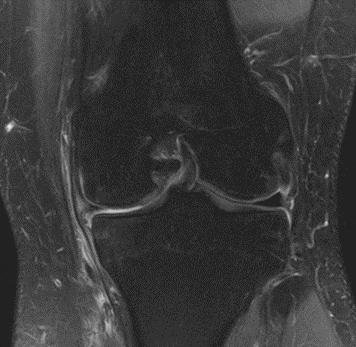

MRI scans illustrating the improvements regarding Group 2 are presented below, showing pre-treatment images with evident cartilage defects, pronounced bone marrow edema, and synovial inflammation, followed by post-treatment scans demonstrating improved joint structure, reduced edema, and decreased inflammation (Figures 12-29).

Figure 12: Female, 59 years, pre-intervention MRI.

Figure 13: Female of figure 12, 59 years, two-month follow-up MRI: MSC plus ChondroFiller® liquid.